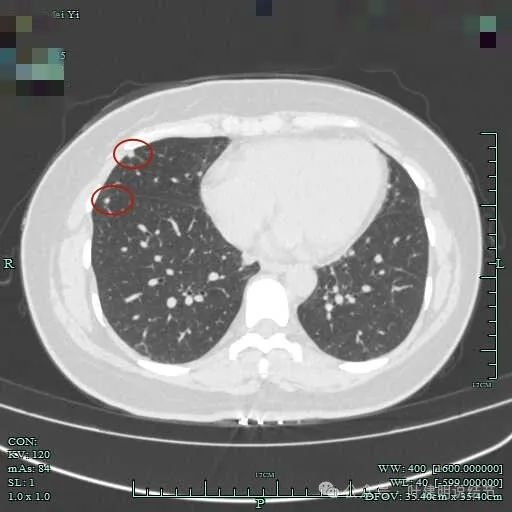

心缘旁另有实性小结节,像良性些。

中叶胸膜下也有小结节,实性。

中叶与下叶胸膜下都有结节。

下叶结节密度较高,边缘有一侧稍模糊。